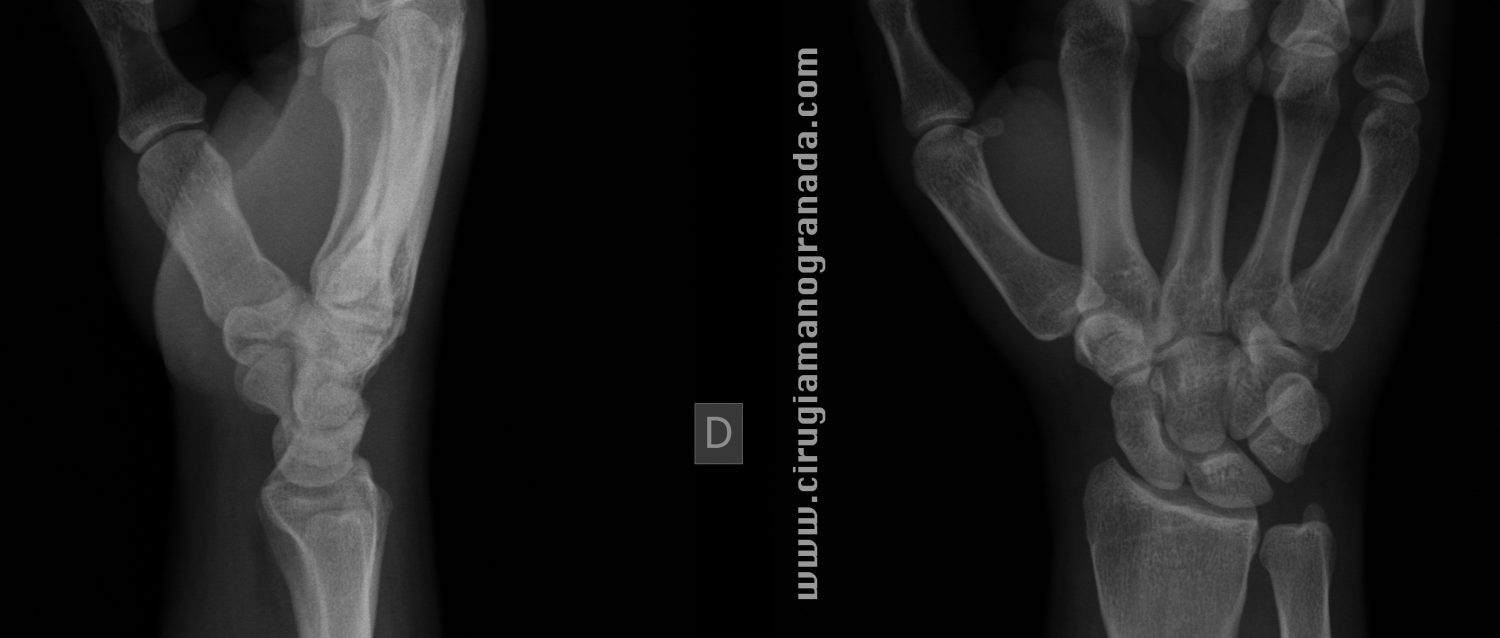

Cirugía de Mano y Traumatología: Pruebas Radiológicas para la fractura

Source: manoytrauma.blogspot.com